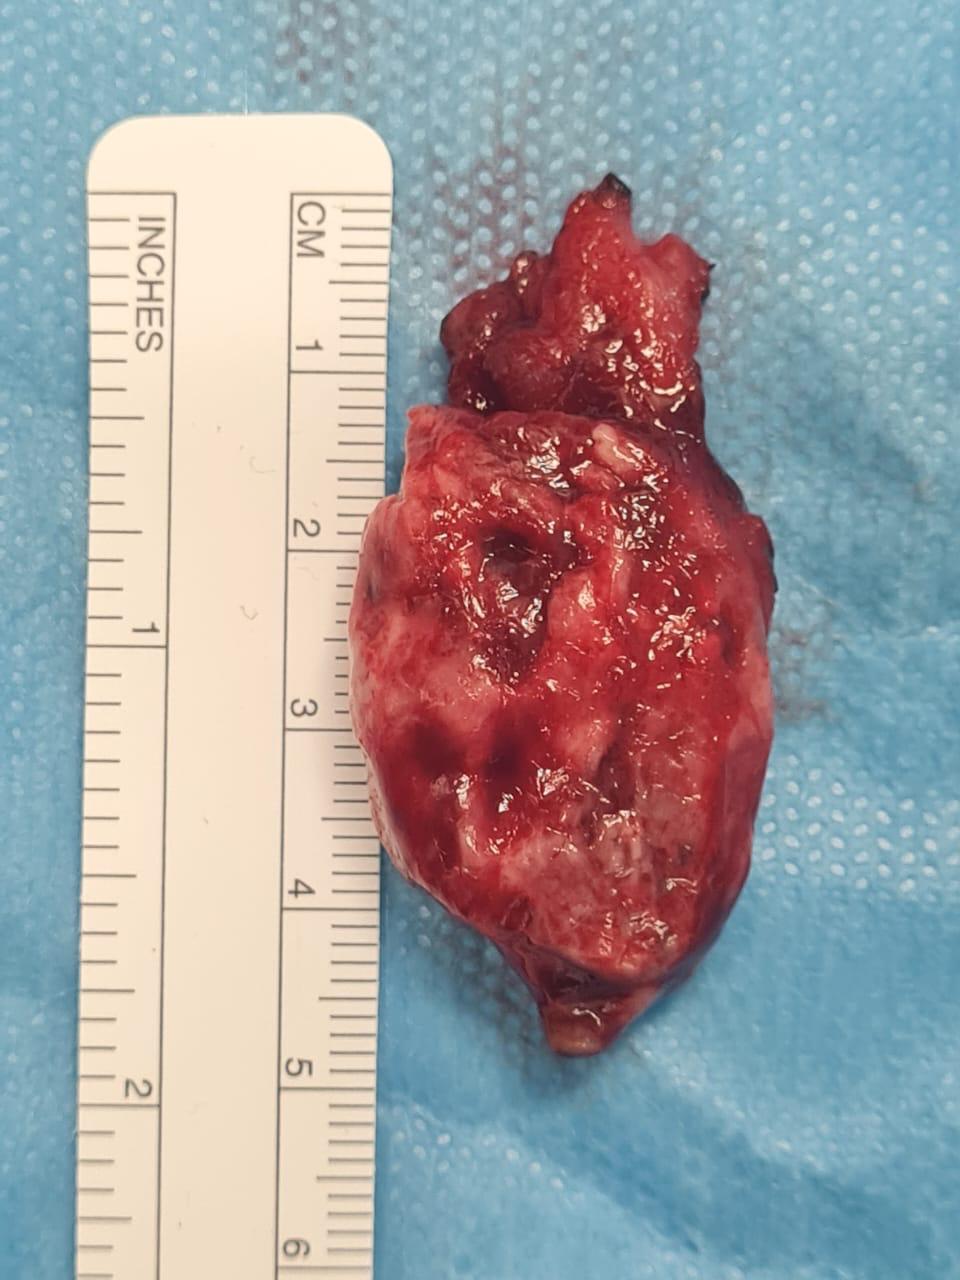

نجح فريق طبي تكاملي بمدينة الملك عبدالله الطبية عضو تجمع مكة المكرمة الصحي وبالتعاون مع مستشفى الولادة والأطفال في إجراء عميلة معقده لمواطنة في العقد الثالث من العمر حامل في الشهر الثامن كانت تعاني من وجود ورم وعائي انفي بدء في الظهور خلال فترة حملها.

واستقبلت المدينة الطبية المريضة والتي بدأت تشكو من أعراض إنسداد الانف والنزيف المتكرر مع بداية الثلث الثاني من الحمل والتي تعتبر من الحالات النادرة التي قد تحدث خلال فترة الحمل ويعود السبب في ذلك الى ارتفاع الهرمونات، وتمت مراجعة حالة المريضة واجراء التحاليل والفحوصات والأشعة اللازمة والتي أظهرت نتائجها وجود ورم وعائي بمنطقة الأنف يستوجب معه الاستئصال. وقد تم اتخاذ القرار بضرورة التدخل الجراحي وانهاء الحمل بولادة الطفل مبكراً قبل الموعد بسبب تضخم الورم الذي شّكل خطورة على الام بسبب النزيف الانفي الحاد والمتكرر.

وأجتمع الفريق الطبي بوضع الخطة العلاجية حيث تم الاستعانه بفريق طبي بالتعاون مع مستشفى الولادة والاطفال وذلك لإجراء العملية القيصرية عن طريق فريق جراحة النساء و الولادة و الاطمئنان والتأكد من سلامة الجنين عن طريق فريق حديثي الولادة فيما تلاه بعد ذلك قيام فريق جراحة مناظير الأنف و قاع الجمجمة بالمدينة الطبية بإستكمال عملية إستئصال الورم الأنفي الوعائي بالكامل ولله الحمد حيث تم نقل المولود الى حضانة مستشفى الولادة والاطفال بعد اجراء الكشف والفحوصات اللازمة والتي بينت أنه يتمتع بصحة جيده وكذلك الأم التي تماثلت للشفاء وخرجت وهي بتمام الصحة والعافية ولله الحمد.